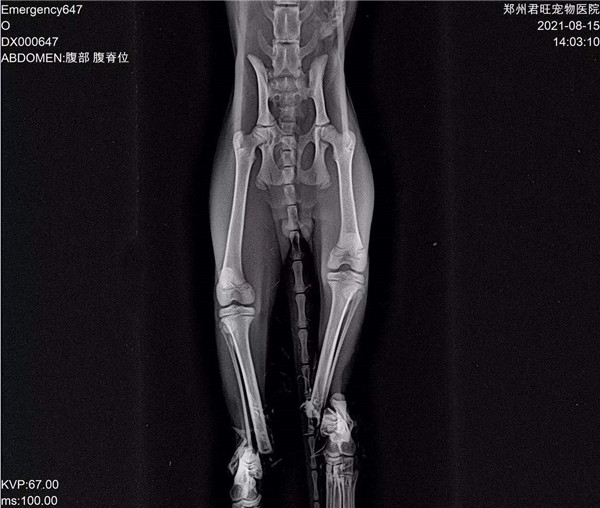

郑州市君旺宠物医院的翟医生,望着眼前面目全非的九福,微微锁起了眉头,简单检查过之后,就得出了判断:九福是被人虐待了。因为它的四条腿均是对称性骨折,两只前腿更是粉碎性骨折,满口牙也被拔掉了。“这绝对不是车祸,或者动物撕咬造成的,只能是人。”